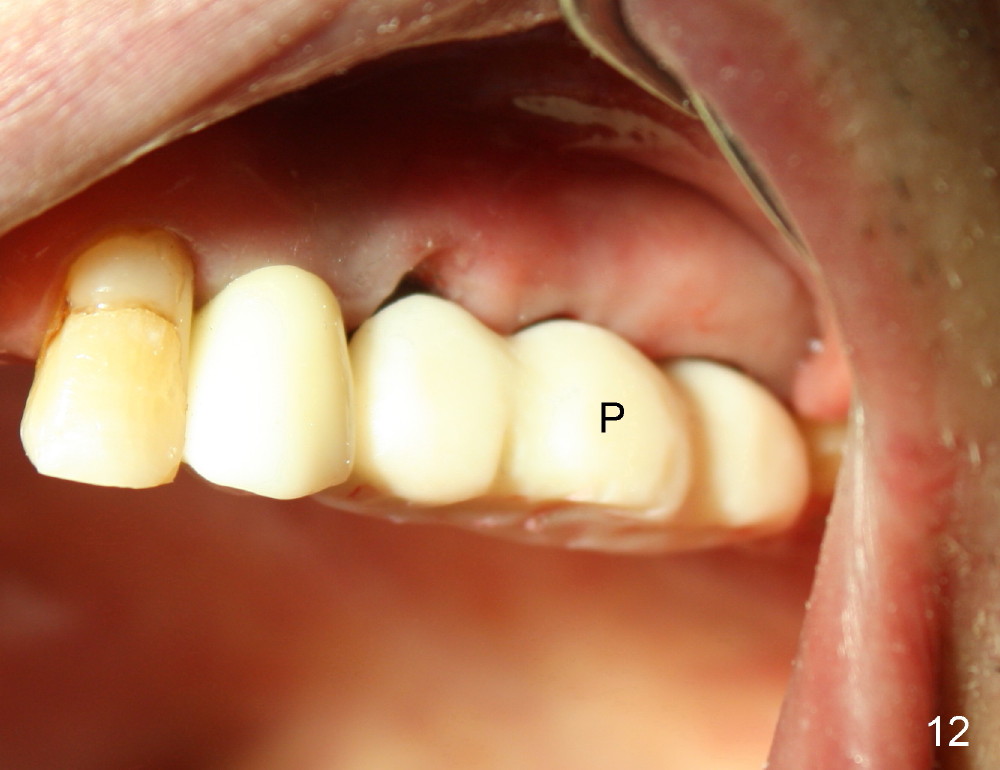

The provisional dislodges once more several days later.  The implant at the site of #14 is uncovered; an abutment (A) is placed (Fig.10.11); a provisional (Fig.12 P) 3-unit bridge is fabricated and cemented securely.  There is some occlusal contact with the opposing teeth.